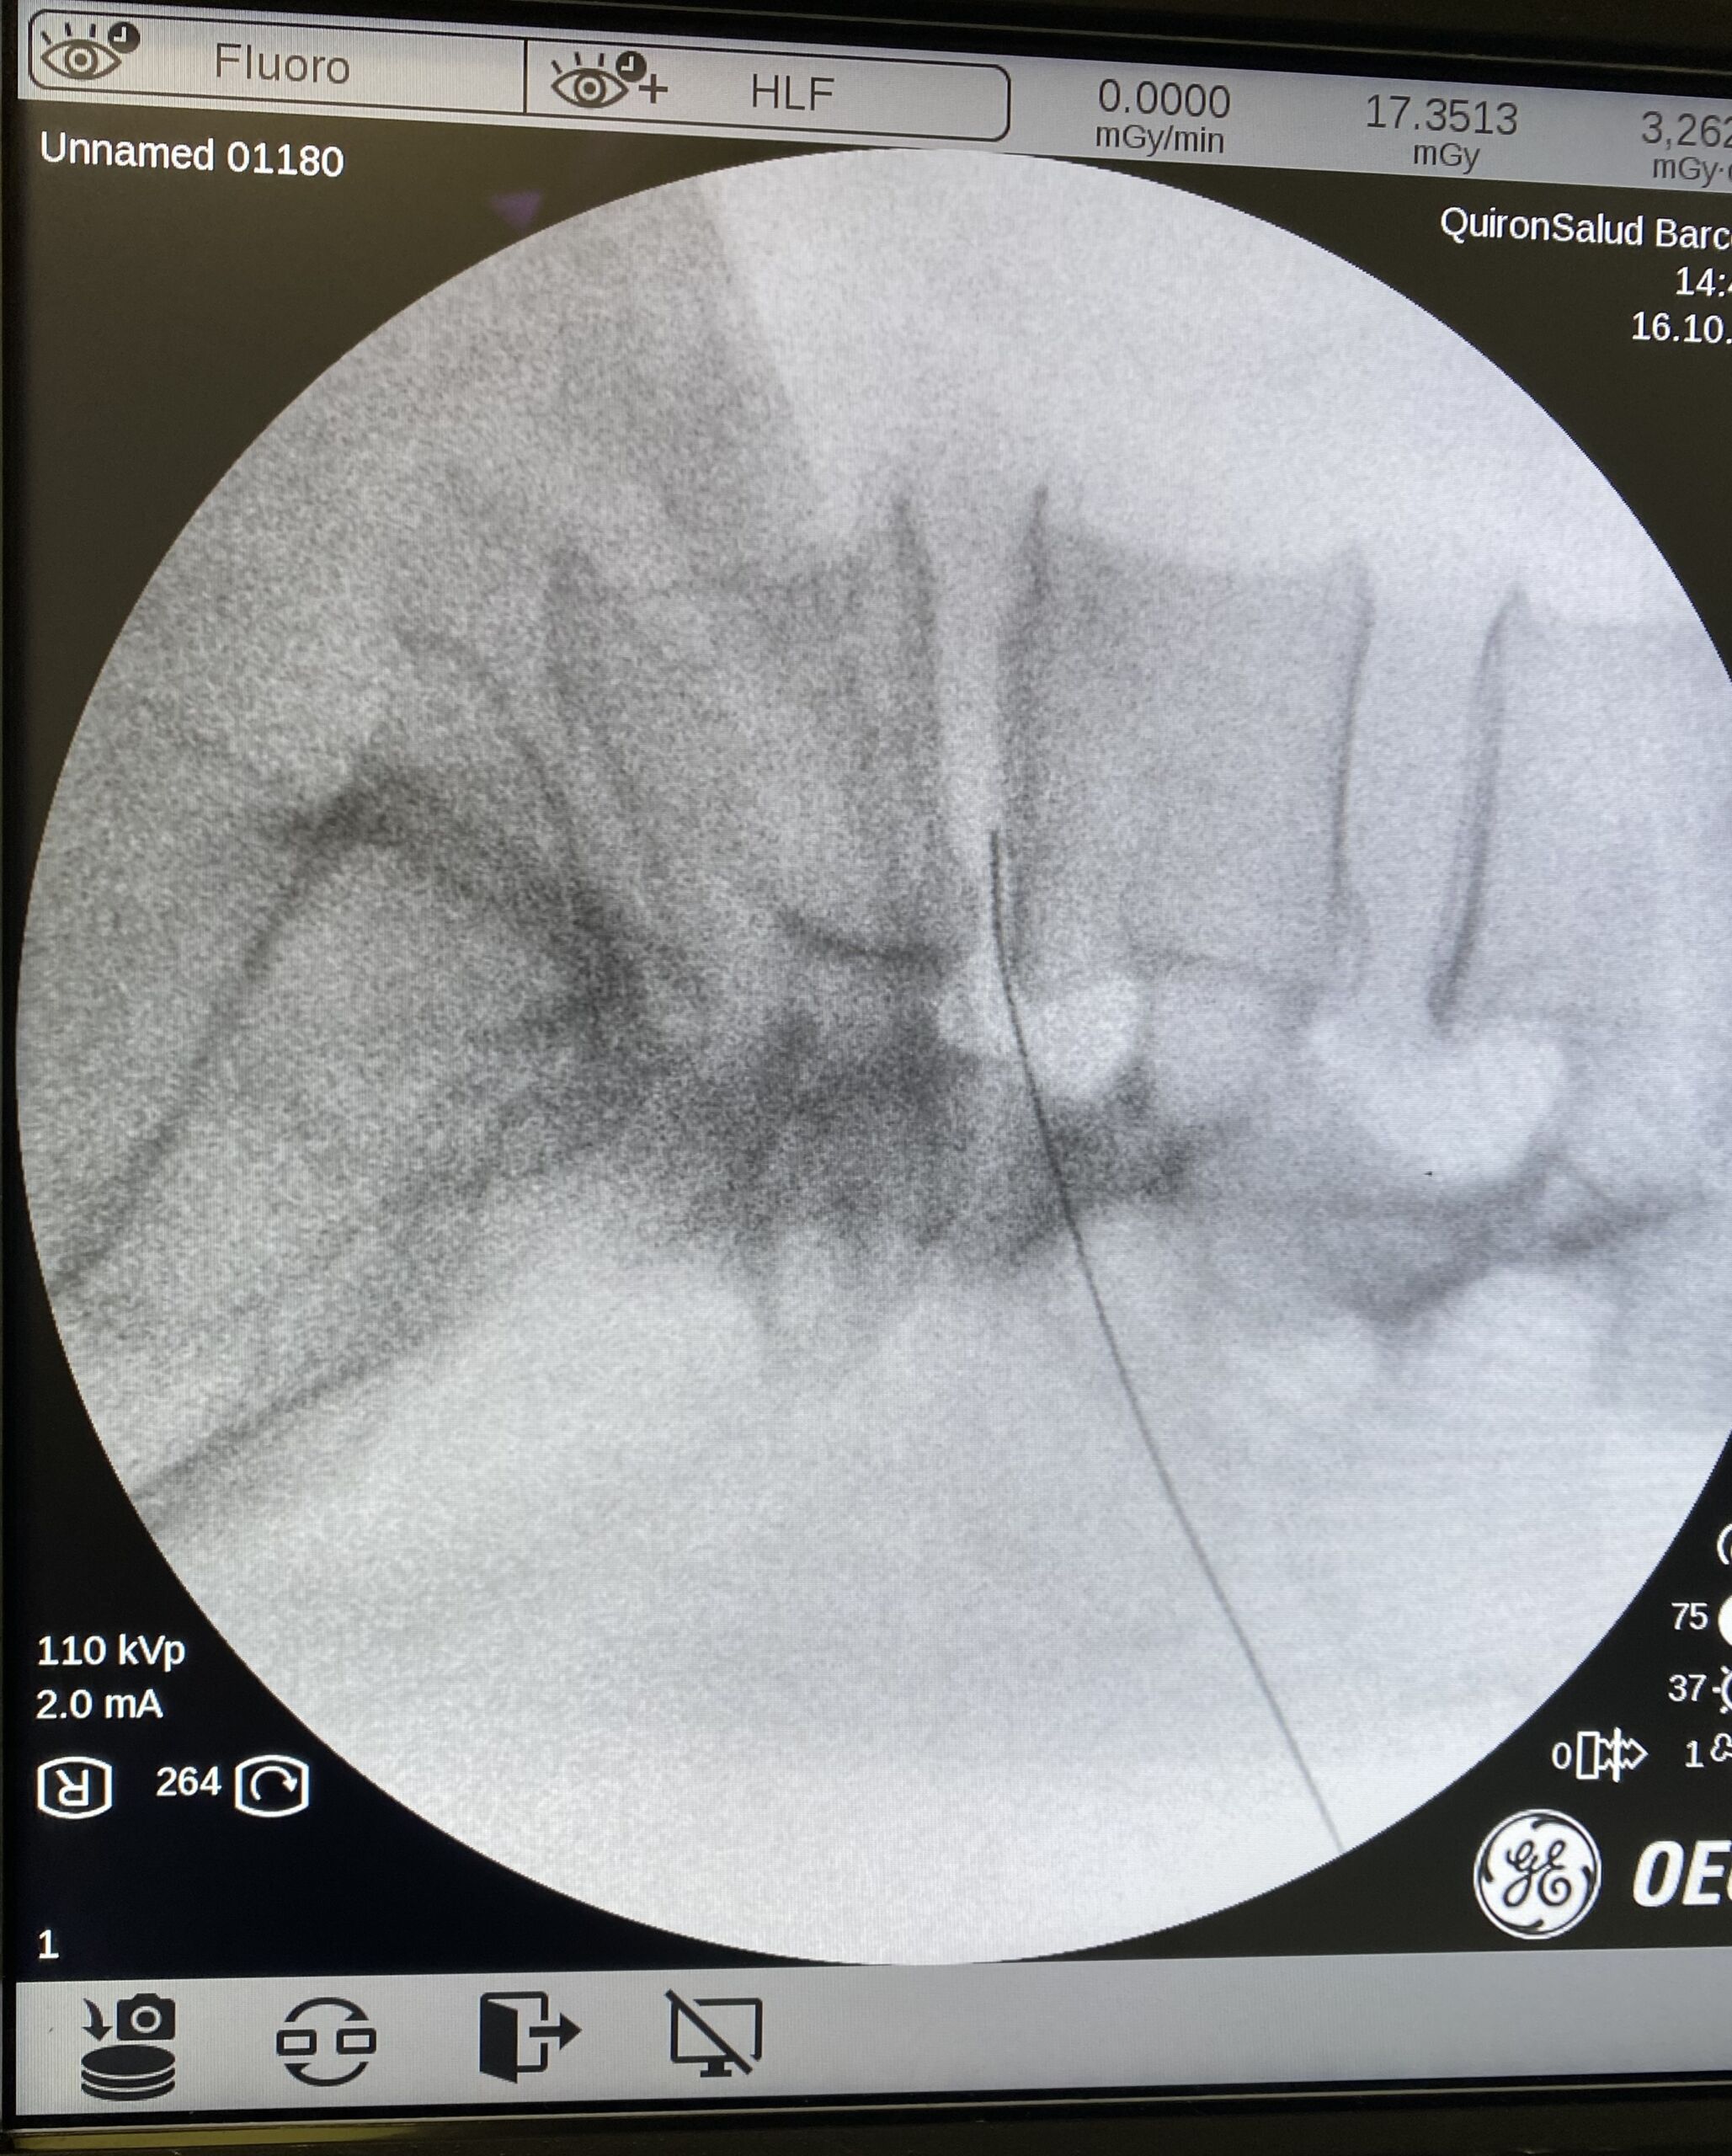

La discolisis con ozono no es una terapia superficial. Consiste en la inyección por parte del neurocirujano de la mezcla de ozono y oxígeno médico directamente en el interior del disco intervertebral herniado, a través de una aguja muy fina, en quirófano y bajo control radiológico preciso.